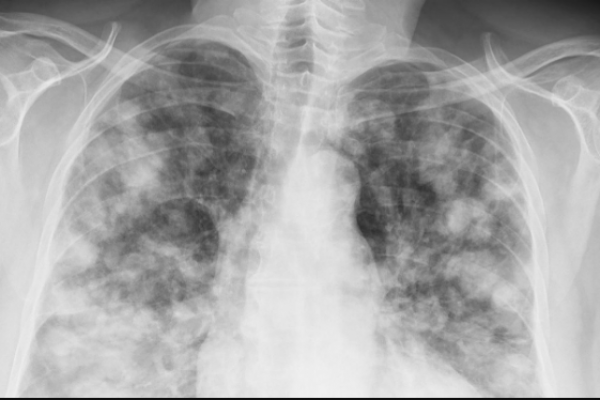

Los tumores digestivos representan una causa importante de morbimortalidad en la población de ambos sexos. Se calcula que en España se detectan aproximadamente 220.000 nuevos casos de cáncer cada año, un 25% de ellos son tumores digestivos. La

incidencia de éstos ha ido variando a lo largo de los años.